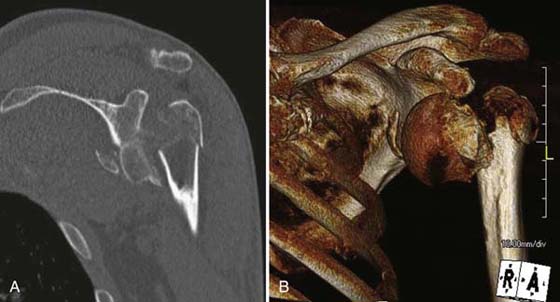

images

Figure 14-3 Comminuted intra-articular fracture. A, Coronal 2D CT image of a comminuted intra-articular right humeral head and glenoid fracture. B, Reconstructed 3D CT image in the same patient improves appreciation of fracture extent and pattern, assisting in operative planning.

CT allows precise characterization of fractures at the shoulder and elbow, defining degree of comminution and displacement, and identifying intra-articular osseous bodies if present. CT arthrography is an alternative to MR arthrography, allowing assessment of rotator cuff tears (especially full-thickness), labral tears, and cartilage loss at the glenohumeral joint (Fig. 14-4).3 CT may also be used for image-guided intervention.